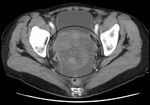

An ovarian cancer as seen on CT. Source: James Heilman, MD, Wikimedia Commons

Ovarian cancer is particularly problematic to treat and diagnose. Ovarian cancer is often only diagnosed when it is already a late-stage cancer because there are no early detection screening methods and because many of the symptoms are not specific to ovarian cancer and are not always gynecological. If ovarian cancer is found early, the five-year survival rate is 92%. However, only 20% of ovarian cancers are detected at an early stage.